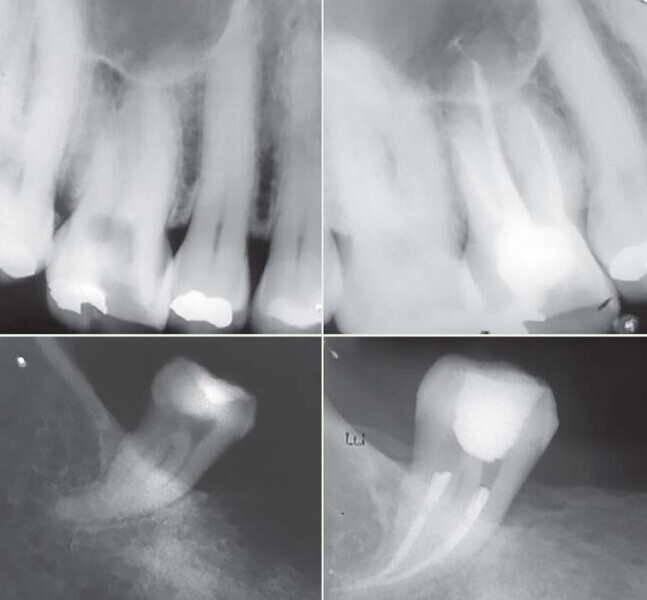

Figs. 1 : Cas clinique réalisé avec le système Genius (c Dr Carlos Spironell Ramos).